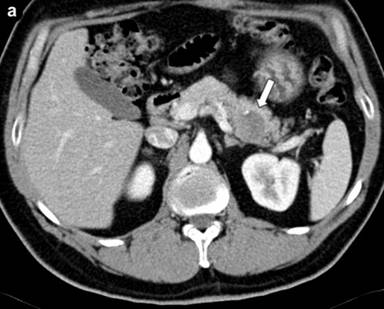

Further etiological investigations were performed, including an abdominal CT which showed a solid mass of 40 mm of diameter with small parietal eccentric calcification located in the body-tail of the pancreas (Figure 1a), encompassing the splenic artery (Figure 1b). Lymph nodes along the small gastric curve, in the inter-aortic and left para-aortic cable, and a calcified lymph node in the lower edge of the liver were also present (Figure 2). No alterations of the other parenchymal organs were detected. A suspicion of pancreatic cancer was pose, although the CA 19-9 was negative (1.6 U/mL; reference range: 0-37 U/mL).

Figure 1. CT shows a solid mass of 40 mm of diameter with small parietal eccentric calcification located in the body-tail of the pancreas (a.) and encompassing the splenic artery (b.) |